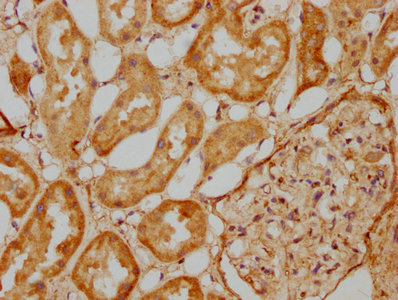

IHC image of CSB-PA880107LA01HU diluted at 1:500 and staining in paraffin-embedded human kidney tissue performed on a Leica BondTM system. After dewaxing and hydration, antigen retrieval was mediated by high pressure in a citrate buffer (pH 6.0). Section was blocked with 10% normal goat serum 30min at RT. Then primary antibody (1% BSA) was incubated at 4°C overnight. The primary is detected by a biotinylated secondary antibody and visualized using an HRP conjugated SP system.